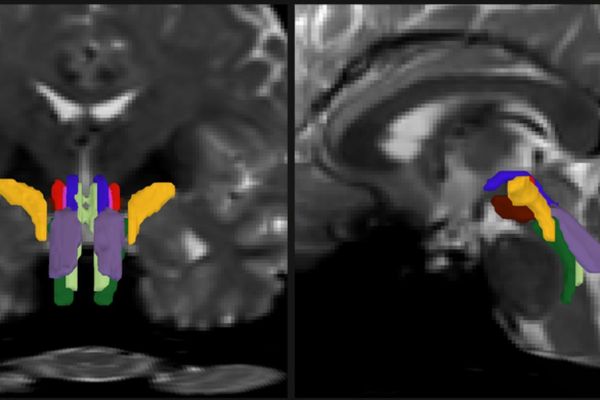

AI Breakthrough Enables First Detailed Mapping of Brainstem White Matter Pathways